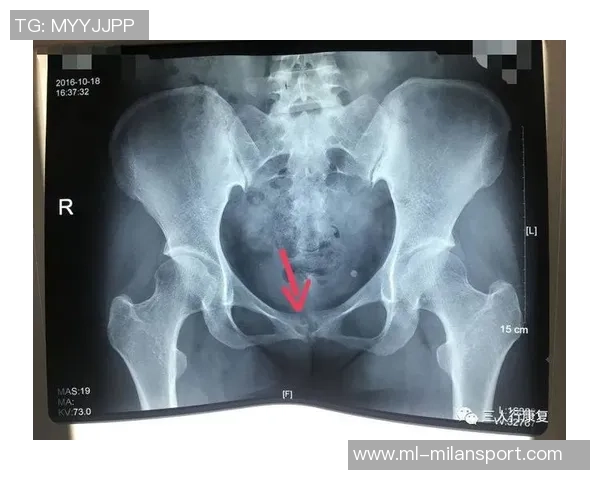

尼科·威廉姆斯是一名备受瞩目的年轻球员,他在比赛中表现出色,为球队贡献了许多关键进球。然而,在一次重要比赛中,他不幸遭遇了耻骨炎。这种疾病给他的训练和比赛造成了严重影响,让他不得不面对漫长而艰难的恢复过程。

初期,尼科并没有意识到自己的伤势有多严重。他依旧坚持参加训练,但随着时间推移,他逐渐感受到身体的不适。经过专业医生的检查后,他被确诊为耻骨炎,这让他深感沮丧,因为这意味着他需要停下脚步,进行长时间的康复治疗。

从确诊开始,尼科·威廉姆斯便积极配合医生制定了一套详细而科学的康复计划。这个计划包括物理治疗、药物调理以及特定动作训练等多个环节,以帮助减轻疼痛和加快康复速度。同时,他也开始注重饮食,通过合理营养来增强身体抵抗力。